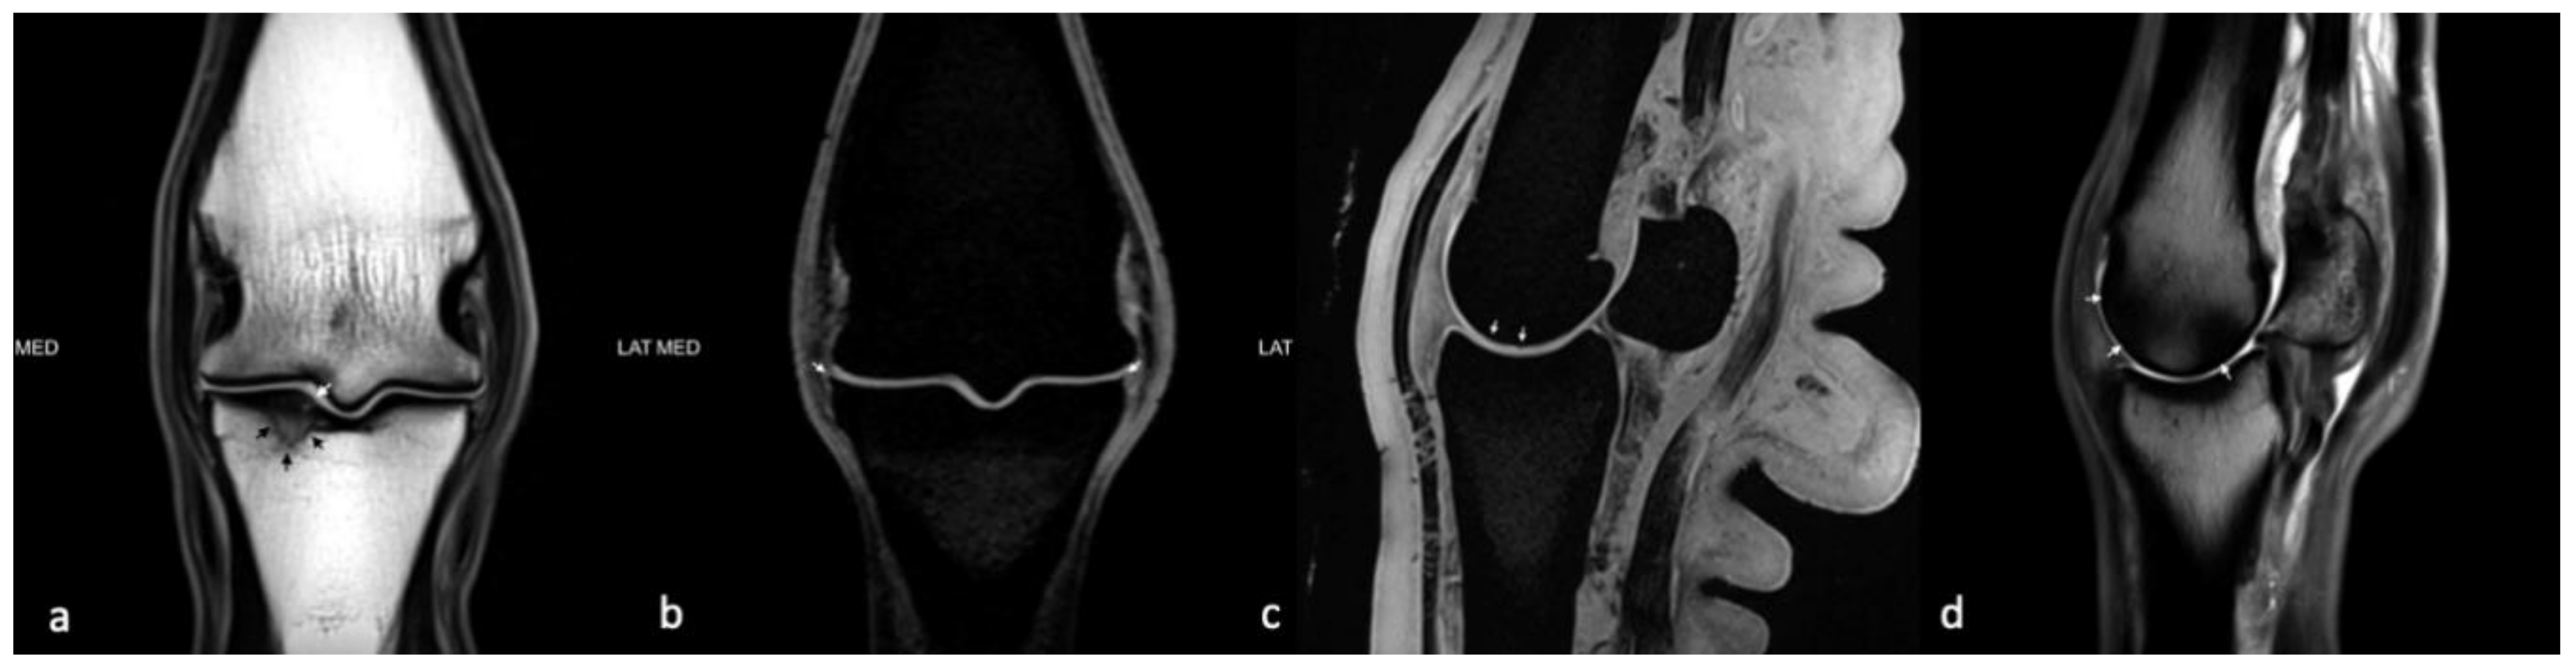

2.2. Magnetic Resonance Imaging